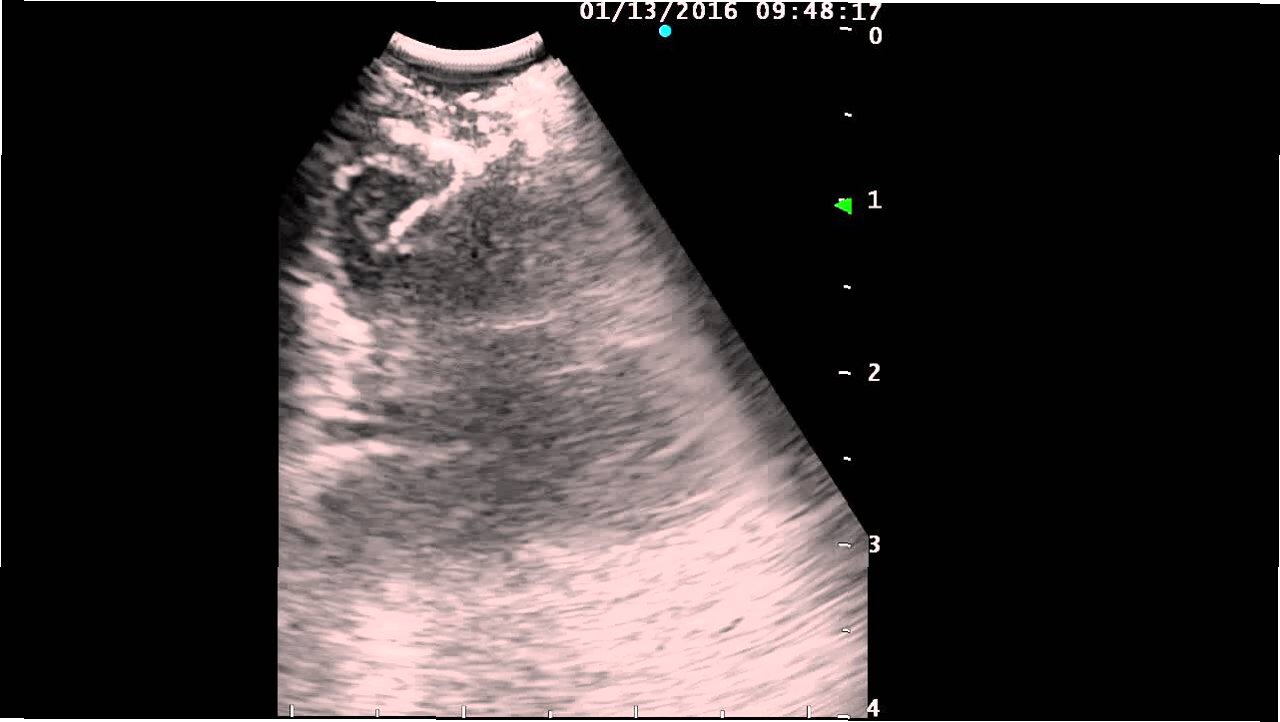

내시경 초음파(EUS, Endoscopic Ultrasound)는 내시경과 초음파 기술을 결합한 최첨단 진단 방법입니다. 일반적인 내시경 검사처럼, EUS는 가느다란 튜브를 식도, 위, 십이지장으로 삽입하여 내부 장기를 직접 관찰합니다. 이 튜브 끝에는 고해상도 초음파 프로브가 장착되어 있어, 내부 장기의 실시간 이미지를 제공합니다. EUS는 림프절을 포함한 주변 조직의 자세한 영상을 얻을 수 있어 림프종 진단에 매우 유용합니다. EUS는 일반적인 초음파 검사보다 더 정확하고, CT나 MRI와 같은 다른 영상 검사보다 더 높은 해상도를 제공하여 작은 병변까지 감지할 수 있습니다.

EUS를 이용한 림프종 진단 과정은 다음과 같습니다. 먼저, 환자는 검사 전에 금식을 해야 합니다. 검사 당일, 환자는 진정제를 투여받아 편안하게 검사를 받을 수 있습니다. 의사는 EUS를 식도, 위, 또는 십이지장으로 삽입하여 림프절을 포함한 주변 조직을 관찰합니다. 초음파 영상으로 림프절의 크기, 모양, 내부 구조 등을 평가하여 림프종의 의심 여부를 판단합니다. 필요에 따라, EUS 유도하 세침 생검(EUS-FNA)을 시행하여 림프절 조직을 채취합니다. 채취된 조직은 병리과에서 분석하여 림프종의 종류를 확진합니다. 검사 후, 환자는 회복실에서 휴식을 취한 후 귀가할 수 있으며, 검사 결과는 추후 외래 진료를 통해 확인합니다.